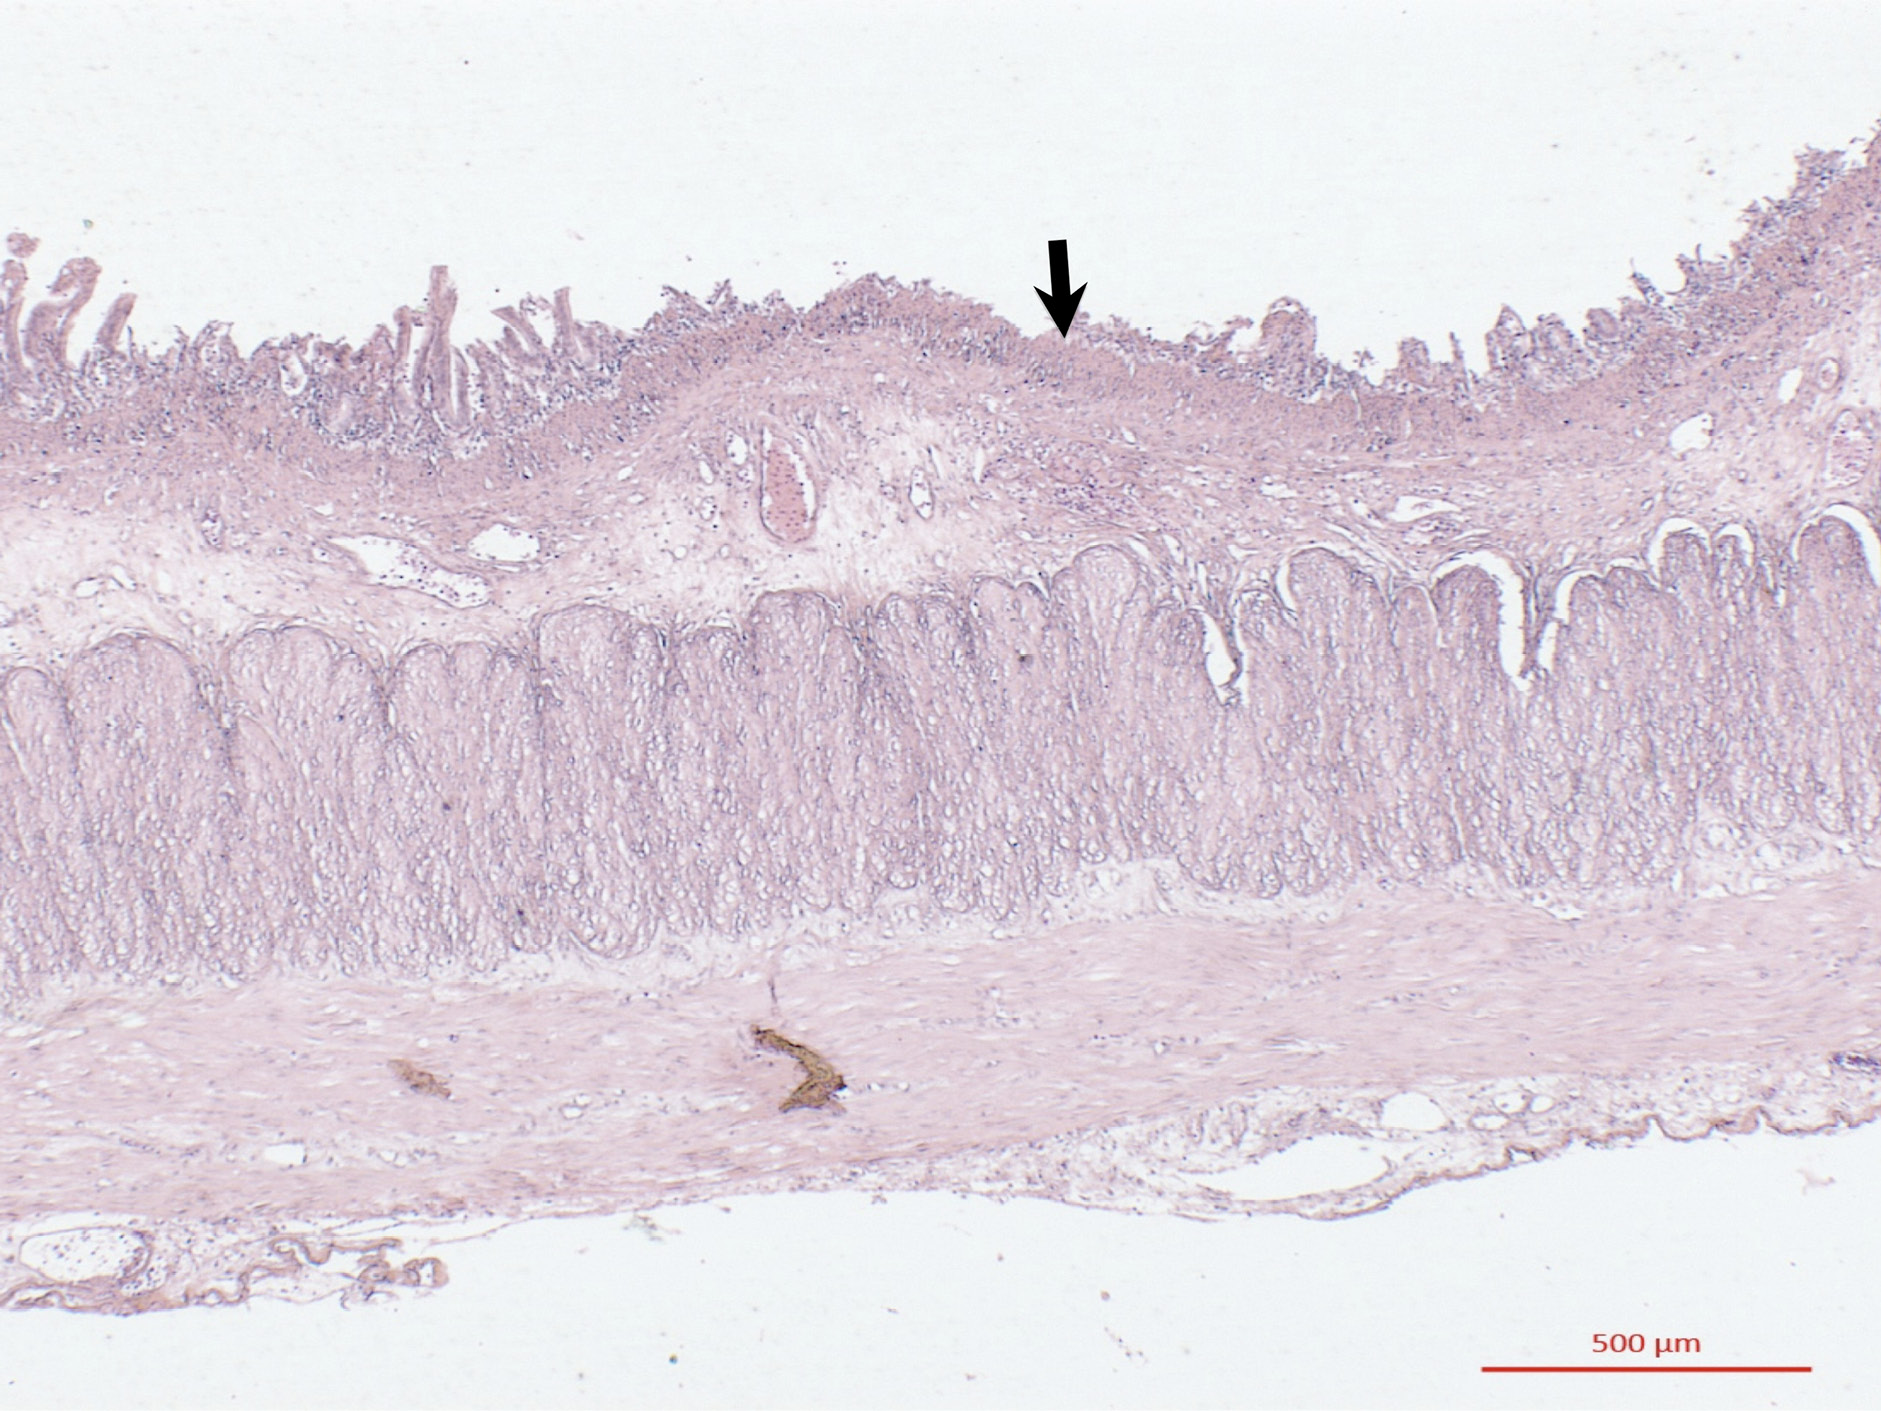

Figura 3

Diagnóstico histológico

Nota. La tinción de hematoxilina-eosina revela una enteritis necrótica hemorrágica (flecha).

La resección de la porción duplicada fue exitosa y el paciente se recuperó adecuadamente. La histopatología confirmó la duplicación mostrando la estructura característica del intestino delgado (Vellosidades intestinales) que además cursaba por un proceso de enteritis necrótica hemorrágica posiblemente en respuesta al contenido intestinal que ocasionaba la obstrucción.